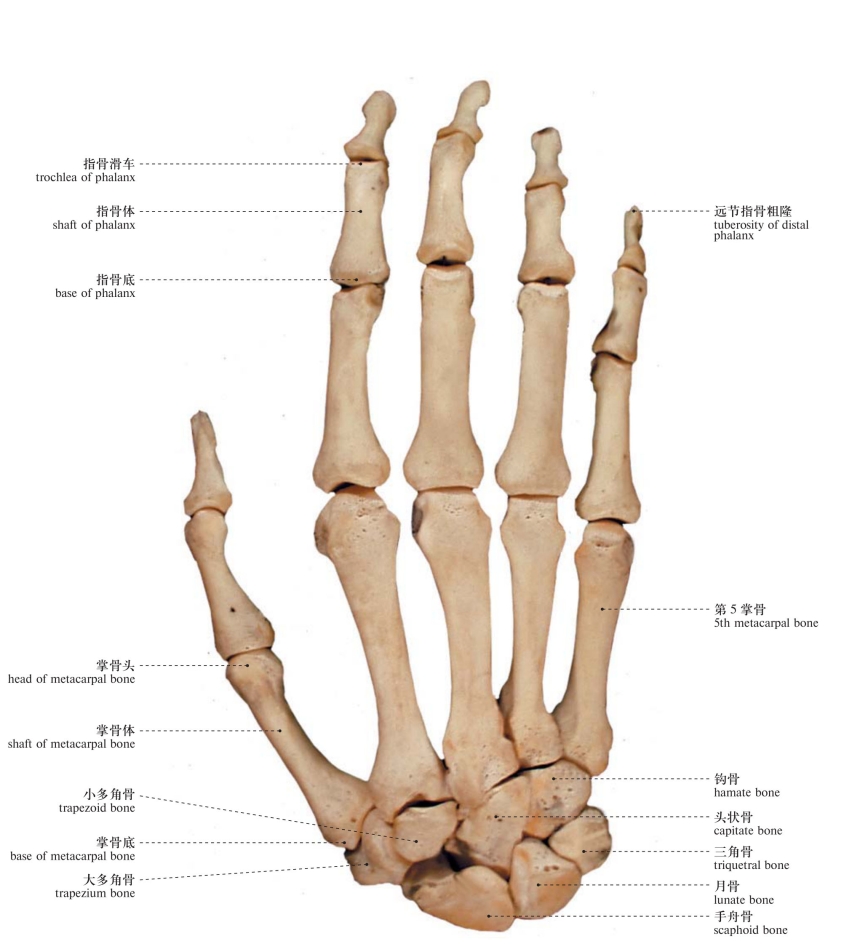

图99 手骨(背面观)

Bones of the hand (dorsal aspect)